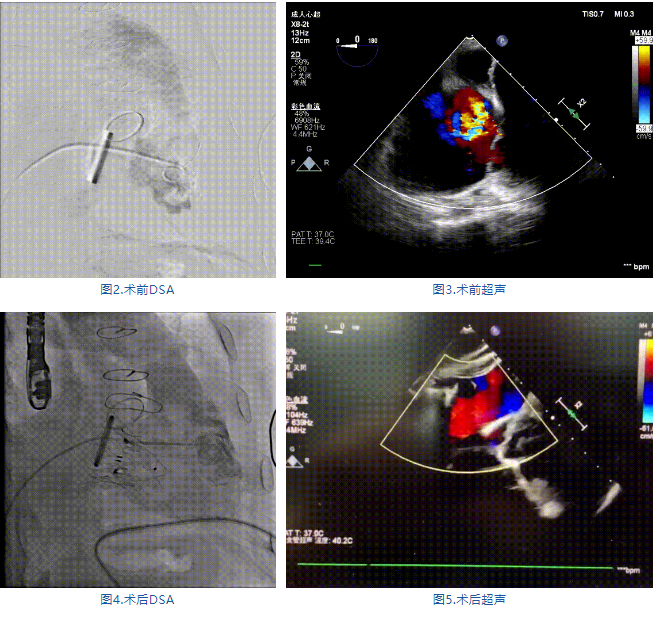

手術(shù)在全麻狀態(tài)下進(jìn)行,郭惠明教授團(tuán)隊(duì)采用經(jīng)右側(cè)頸靜脈入路的方式送入輸送器進(jìn)入體內(nèi),并在TEE和DSA的指引下進(jìn)行。在輸送器進(jìn)入右室后釋放室間隔錨定裝置,旋轉(zhuǎn)輸送器,使得錨定裝置對準(zhǔn)室間隔面;而后釋放前瓣夾持件,確定夾持件位于右室側(cè)釋放LuX-Valve Plus人工瓣膜盤片,再使用DSA和超聲確認(rèn)盤片是否位于右房側(cè),同時調(diào)整瓣膜的同軸性。緊接著在DSA和超聲的監(jiān)視下調(diào)整室間隔錨定件貼合室間隔,釋放室間隔錨定裝置。再次確認(rèn)瓣膜的穩(wěn)定性和同軸性后,將輸送器撤出體內(nèi),最終完成LuX-Valve Plus人工瓣膜植入(圖2-5),手術(shù)獲得圓滿成功?;颊咴谑中g(shù)室即刻拔除氣管插管,術(shù)后超聲提示LuX-Valve Plus人工三尖瓣瓣膜同軸性良好,瓣架固定牢靠,無反流和瓣周漏。